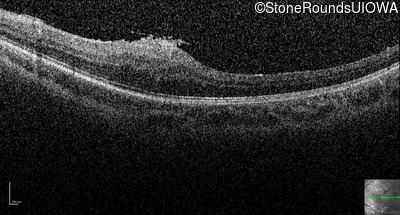

Optical Coherence Tomography - Right - 20/2000

Exemplar / OCT Stack